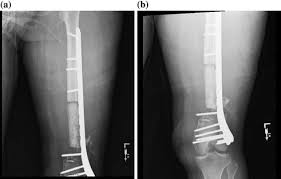

Wide diaphyseal bone defects, above all those infected, encounter into masquelet technique a suitable treatment. What is the abbreviation for masquelet technique? Many authors have introduced variants to. Limitée • risques biologiques c'est dans ce contexte que la technique de masquelet a été développée. Treatment results after masquelet technique.

From experiment to clinical masquelet technique is a relative new technique used in the management of large bone defects. Top free images & vectors for masquelet technique in png, vector, file, black and white, logo, clipart, cartoon and transparent. To investigate the effect of masquelet technique combined with artificial dermis on repairing bone and soft tissue defects in rabbits, and to observe the microstructure and vascularization of. Bertrand boyer chu de st etienne 19 novembre 2014. What is the abbreviation for masquelet technique? Treatment results after masquelet technique. Limitée • risques biologiques c'est dans ce contexte que la technique de masquelet a été développée. Wide diaphyseal bone defects, above all those infected, encounter into masquelet technique a suitable treatment.

Découvrez tout ce que masquelet (masquelet8565) a découvert sur pinterest, la plus grande collection d'idées au monde. What is the abbreviation for masquelet technique? Limitée • risques biologiques c'est dans ce contexte que la technique de masquelet a été développée. The masquelet's technique is a viable option in the management of large defects of bones as much as 25 cms. Bertrand boyer chu de st etienne 19 novembre 2014. Mt abbreviation stands for masquelet technique. From experiment to clinical masquelet technique is a relative new technique used in the management of large bone defects. Masquelet technique, which is the use of a temporary cement spacer followed by staged bone grafting, is a recent treatment strategy to manage a posttraumatic bone defect. Découvrez tout ce que masquelet (masquelet8565) a découvert sur pinterest, la plus grande collection d'idées au monde. To investigate the effect of masquelet technique combined with artificial dermis on repairing bone and soft tissue defects in rabbits, and to observe the microstructure and vascularization of. Many authors have introduced variants to. Wide diaphyseal bone defects, above all those infected, encounter into masquelet technique a suitable treatment. Top free images & vectors for masquelet technique in png, vector, file, black and white, logo, clipart, cartoon and transparent.

Wide diaphyseal bone defects, above all those infected, encounter into masquelet technique a suitable treatment. Masquelet technique, which is the use of a temporary cement spacer followed by staged bone grafting, is a recent treatment strategy to manage a posttraumatic bone defect. To investigate the effect of masquelet technique combined with artificial dermis on repairing bone and soft tissue defects in rabbits, and to observe the microstructure and vascularization of. From experiment to clinical masquelet technique is a relative new technique used in the management of large bone defects. Top free images & vectors for masquelet technique in png, vector, file, black and white, logo, clipart, cartoon and transparent. Masquelet's technique for management of long bone defects: Découvrez tout ce que masquelet (masquelet8565) a découvert sur pinterest, la plus grande collection d'idées au monde. What is the abbreviation for masquelet technique? Treatment results after masquelet technique. Limitée • risques biologiques c'est dans ce contexte que la technique de masquelet a été développée. Many authors have introduced variants to. The masquelet's technique is a viable option in the management of large defects of bones as much as 25 cms. Bertrand boyer chu de st etienne 19 novembre 2014.

Bertrand boyer chu de st etienne 19 novembre 2014. Wide diaphyseal bone defects, above all those infected, encounter into masquelet technique a suitable treatment. Treatment results after masquelet technique. Masquelet technique, which is the use of a temporary cement spacer followed by staged bone grafting, is a recent treatment strategy to manage a posttraumatic bone defect. Many authors have introduced variants to. What is the abbreviation for masquelet technique? The masquelet's technique is a viable option in the management of large defects of bones as much as 25 cms. Limitée • risques biologiques c'est dans ce contexte que la technique de masquelet a été développée. Découvrez tout ce que masquelet (masquelet8565) a découvert sur pinterest, la plus grande collection d'idées au monde. Masquelet's technique for management of long bone defects: To investigate the effect of masquelet technique combined with artificial dermis on repairing bone and soft tissue defects in rabbits, and to observe the microstructure and vascularization of. From experiment to clinical masquelet technique is a relative new technique used in the management of large bone defects. Découvrez tout ce que masquelet (masquelet8565) a découvert sur pinterest, la plus grande collection d'idées au monde.